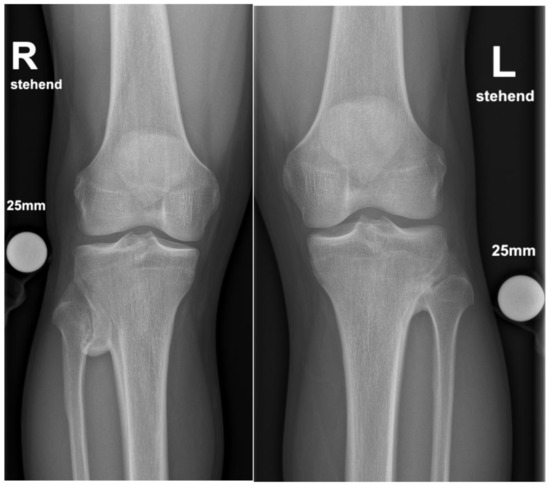

In supine position and under general anesthesia, both lower extremities were washed and draped in sterile cloth. Surgery was started using Esmarch’s-Method on the left side. The approach was direct anterolateral towards the tibiofibular joint, about 4cm in length. Passing the subcutaneous fat tissue, the crural fascia was dissected, and the proximal part of the anterior tibial muscle was pushed medially and retracted with hooks. Then, the synostosis was visible. The surface of the synostosis was primed with a rasp, and a Hohmann hook was placed proximal and distal. Then, the synostosis was excised with a chisel and a Luer pincer. The gap between the tibia and fibula was considered to be broad enough when a distance of 5mm was reached (Figure 4). Then, the situs was flushed with saline, bone wax was stuck to the open fibular and tibial bone to prevent reossification, and stepwise closure of the wound was performed. A drain was used. The procedure was then performed on the right side in the same way. A postoperative biplane X-ray was performed (Figure 5).

Figure 5. Plain radiograph in a.-p. view after resection.